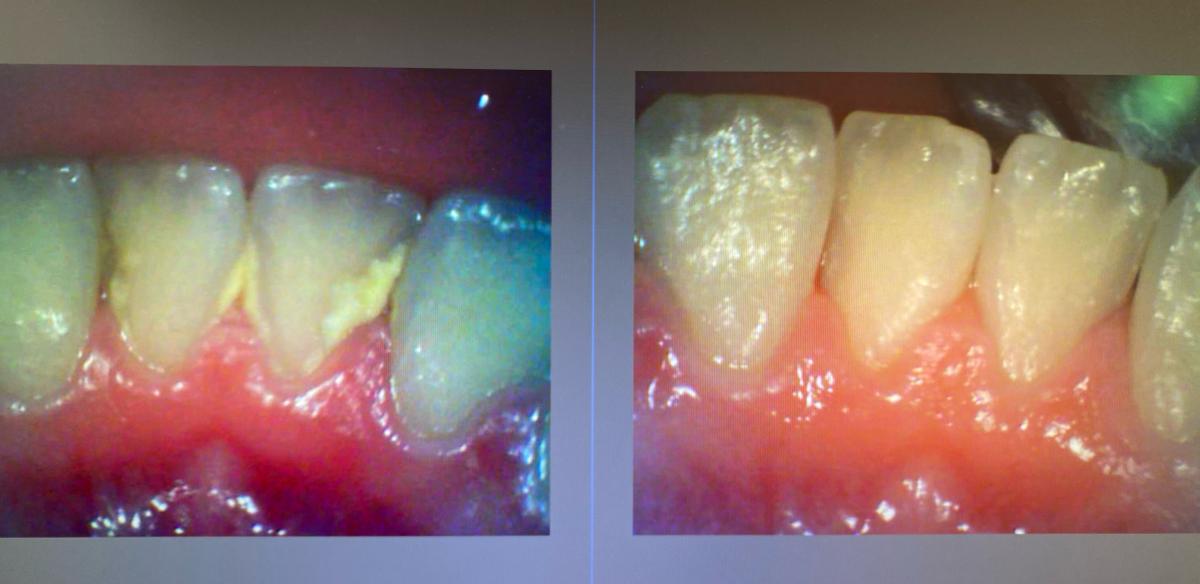

左側の写真は歯の裏側に歯石が

沢山付いてしまっています。

右は機械でクリーニングした後です。

歯石が付いてるいるのは

自分では気づきずらいです。

定期的に歯医者さんに通って

ツルピカの歯を目指しましょう(^^)v